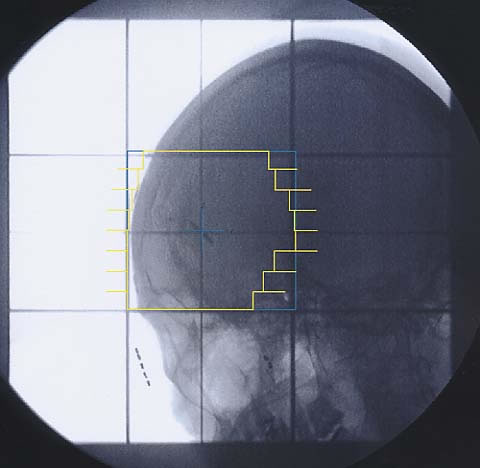

Hirntumore: Simulationsbild